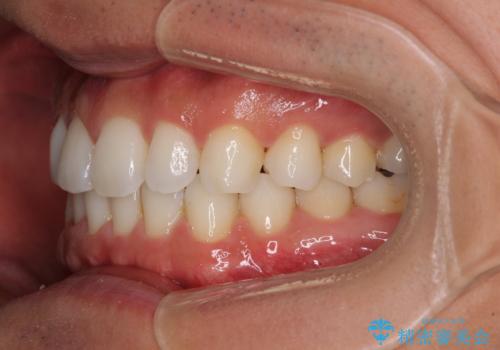

- 上下前歯のデコボコを気にして来院された患者様です。

以前矯正をした後戻りということで、歯列不正はそれほど大きくなかったため、インビザライン・ライトを用いて矯正治療を行うこととしました。

1日22時間以上しっかりと装着してくださったので、半年かからずに治療を終えることができました。